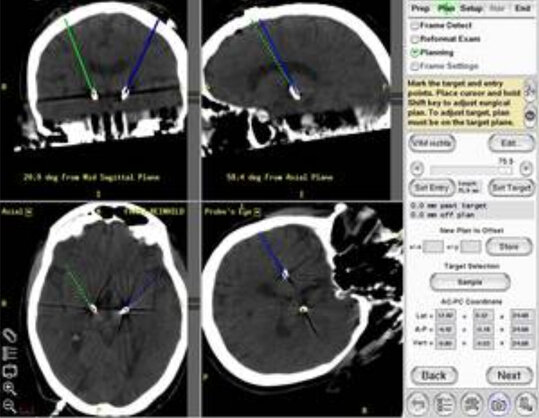

Die Zielstrukturen hängen von der Art der Erkrankung ab. Ein wichtiger Zielpunkt zur Behandlung des reinen Zitterns (Tremor) ist der VIM Kern (Ncl. ventralis intermedius) des Thalamus. Die blaue Linie in Abbildung 7 zeigt den Zugang und die Spitze den Zielpunkt im VIM Kern des Thalamus in einem frontal Hirnschnitt. Wenn bei Morbus Parkinson neben dem Tremor auch Steifigkeit (Rigor), unkontrollierte Bewegungen (Hyperkinesen) oder Bewegungseinschränkung (Akinese) vorliegen, denn werden alle diese Symptome am wirkungsvollsten in einem kleinen Kern zwischen dem Thalamus und dem Mittelhirn ausgeschaltet, dem sog. STN (Ncl. subthalamicus).

Einige Tage vor der Operation wird anhand aktueller Kernspinbilder (MR) die Planung durchgeführt. Bei Morbus Parkinson müssen typischerweise beidseitig Elektroden in den Nukleus subthalamicus (STN) eingeführt werden. Die Software ermöglicht den Zielpunkt im STN in den entsprechenden Schichten darzustellen und den Zugang so zu planen, dass man Verletzung von Gefäßen oder wichtigen Hirnstrukturen vermeidet.

Am Operationstag wird zuerst in Intubationsnarkose der stereotaktischer Grundring am Patientenschädel befestigt und CT unter stereotaktischen Bedingungen gefahren. Diese CT-Bilder werden auf dem Planungsrechner mit den MR-Planungsbildern fusioniert und die Koordinate des Zielpunktes im Verhältnis zum aufgesetzten Grundring ermittelz. Gleichzeitig werden 4 Winkel und die Nadeltiefe berechnet, die auf dem Zielbügel eingestellt werden müssen, um den Zielpunkt zu erreichen.